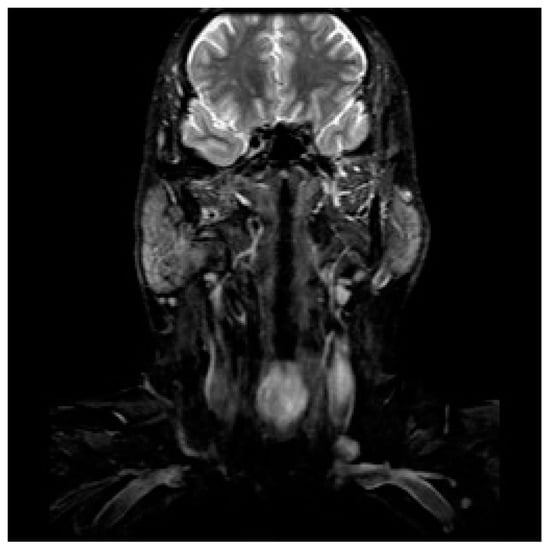

3.1. Diagnostic Workup

- Doğan, S.; Vural, A.; Kahriman, G.; İmamoğlu, H.; Abdülrezzak, U.; Öztürk, M. Non-squamous cell carcinoma diseases of the larynx: Clinical and imaging findings. Braz. J. Otorhinolaryngol. 2020, 86, 468–482. [Google Scholar] [CrossRef]

- Banko, B.; Đukić, V.; Milovanovic, J.; Kovač, J.; Artiko, V.; Maksimović, R. Diagnostic significance of magnetic resonance imaging in preoperative evaluation of patients with laryngeal tumors. Eur. Arch. Oto-Rhino-Laryngol. 2011, 268, 1617–1623. [Google Scholar] [CrossRef]